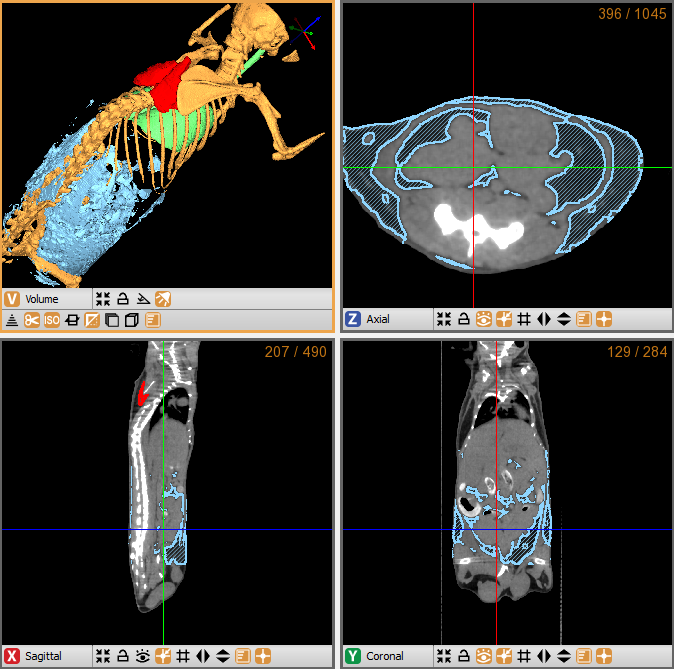

CASE 2: Contrast enhanced CT rat imaging

workimg

• Courtesy of: D.Panetta and P.A. Salvadori, IFC-CNR Pisa, Italy

Research objective: Rat CT imaging with contrast enhancement

Animal model: Wistar rat, ~300g

Acquisition protocol: 90 s acquisition time, 65 kVp, 1 mA, 1 bed position

Processing and reconstruction protocol: 0.06 mm isotropic voxel size

Biomarker or contrast agent: Continuous infusion of Iomeron(TM), 200 mgI/ml, 24 mL/h, 8 min infusion time; CT imaging time: 0 (basal), 4 min and 8 min after beginning of infusion (3D rendering refers to 4 min)